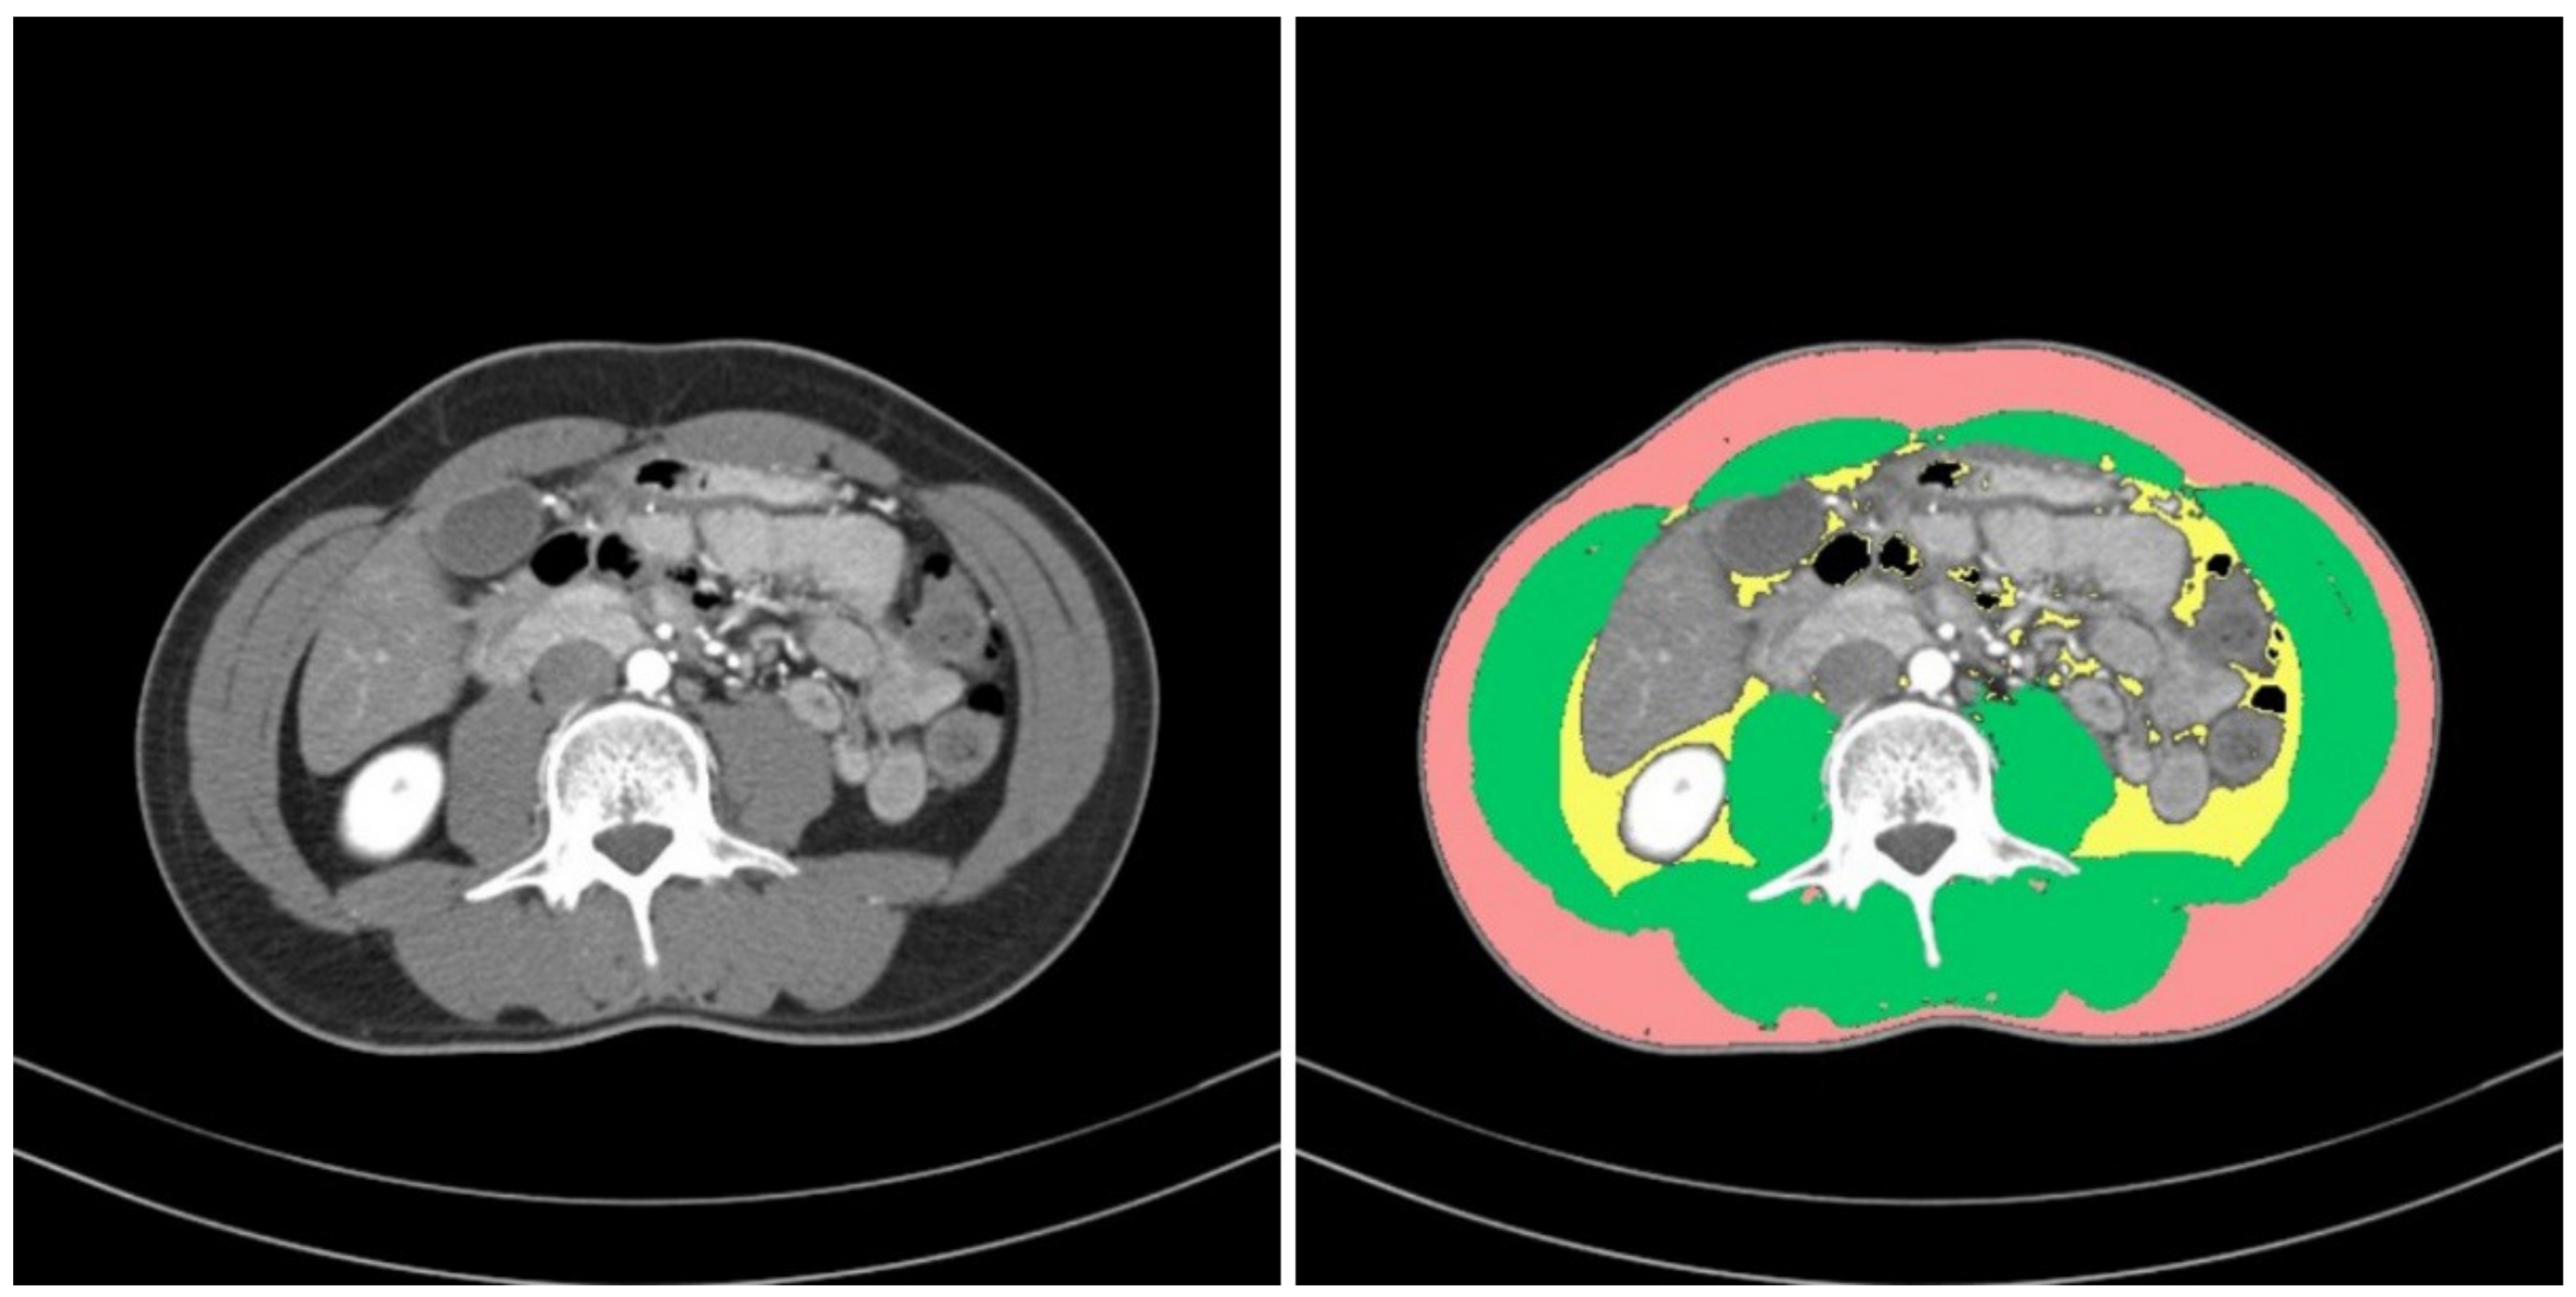

To define sarcopenia, we quantified the muscular areas using an in-house-developed software program (Gachon_DeepBody, developed in the GCUMC, Incheon, Korea) and the collected L3 CT images. Gachon_DeepBody automatically extracts the images of muscles, subcutaneous fat, and visceral fat through a trained U-Net-based deep learning model and provides the areas of each body component [13] (see Figure 2). Using the software program, we automatically identified the muscles in the CT images and secured the muscular areas at the L3 level by manually correcting the erroneously identified areas. The identified areas were also reviewed and corrected by a radiologist with 13 years of experience.

Figure 2. Areas of body components identified by Gachon_DeepBody: muscle (green), subcutaneous fat (red), visceral fat (yellow).